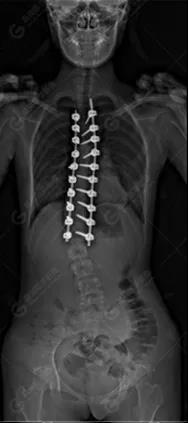

15歲女性,發(fā)現(xiàn)特發(fā)性脊柱側(cè)彎3年,于2019年1月23日來(lái)到廣東高尚醫(yī)學(xué)影像診斷中心行EOS檢查,2019年2月行手術(shù)治療后多次到中心行EOS復(fù)查。

2019-01-23

脊柱側(cè)彎最重要一個(gè)臨床參數(shù)是側(cè)彎角(Cobb角),目前臨床公認(rèn)的Cobb角>10 °診斷為脊柱側(cè)彎;如Cobb角進(jìn)行性持續(xù)性增加>40 °需要手術(shù)矯正治療。

本例患者胸椎右側(cè)彎,Cobb角(T6/T12)為47°,遂行手術(shù)矯正治療。術(shù)后多次隨訪的Cobb角(T10/L3)為12°-15°之間,較術(shù)前明顯縮小。